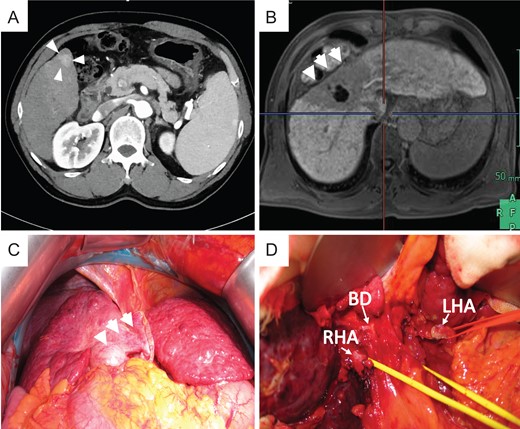

In 2014, she was administered CIRT with a total of 60 Gy (relative biological effectiveness) given in four fractions because of rapidly enlarged tumor with segmental portal vein invasion, as shown on contrast-enhanced computed tomography. Before admission, CT revealed a new recurrence tumor in the lateral segment of the left lobe (Fig. 1A). The irregular surface and unsmooth liver edge also showed LC. Furthermore, severe atrophy was obvious at the CIRT area (Fig. 1A). Because of the new lesion in the left lobe located close to the heart and the underlying liver failure with C-P grade B (9 points), LDLT was performed with an extended left lobe graft from her son in 2015. During surgery, strong adhesion between the thoracic diaphragm and the irradiated lesion in Segment 7 was observed, which resulted in difficulty with adhesiolysis (Fig. 1B). If we preserve the diaphragm, it might be injured irradiated liver during adhesiolysis. We intensively choose a part of diaphragm resection with liver, also protected inferior vena cava (IVC) from injury during resection of diaphragm. We checked where the IVC existed in the thoracic cavity and preserved the IVC above the liver, encircling the right hepatic vein (RHV) after mobilization of the liver. The diaphragm was then repaired directly by suturing. After reconstruction of the hepatic vein (HV), portal vein (PV), hepatic artery and bile duct, we successfully finished the operation. The surgery took over 11 h to complete, and the total amount of blood lost was 2500 g with 10 units of fresh-frozen plasma transfusion (FFP). The specimens showed no HCC recurrence in the CIRT area but did show severe fibrosis (Fig. 2).

Preoperative photograph and intraoperative images of case 1. (A) Liver atrophy was noted in the CIRT area (arrow), and a new lesion (triangle) was noted in the left lobe on preoperative CT. (B) Intraoperative imaging showed strong adhesion between the thoracic diaphragm and the CIRT area.